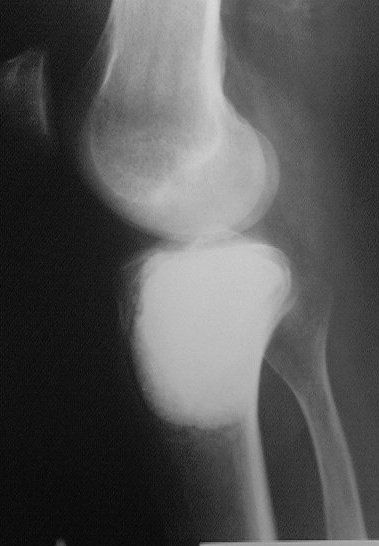

Около года назад больному 25 лет по поводу литической опухоли мыщелка б\б кости ( ОБК?)с выраженным болевым синдромом была произведенарасширенная открытая биопсия, экскохлеация опухоли.

В связи с неясностью диагноза до операции и отсутствия аллокости в тот момент интраоперационно было выполнено экспресс протезирование дефекта мыщелка акриловым цементом. Верхней стенкой дефекта была визуально неповрежденная суставная поверхность. Хрящевая пластина провисала - была выведена на уровень и "подперта" цементным спейсером. Больной осмотрен через год - ходит не хромая, сустав абсолютно спокойный, рентгенологически процедива опухоли нет. Хотелось бы услышать предложения по пластике дефекта - сроки, вид материала. Честно говорябоюсь трогать хрящ повторно.

Случай очень интересный! Увидеть бы снимки до операции. Можно обсудить состояние хряща "на цементе"-за счет чего он жив или там все-таки дефект? Щель сустава хорошая. Есть ли возможность проведения МРТ у больного?

Субхондральное эндопротезирование костным цементом при доброкачественных опухолях давно используется в институте им. Вредена. Редко бывают рецидивы (костный цемент, полимеризуясь, нагревается до 70 градусов). Сроки наблюдений благополучного исхода более 20лет.